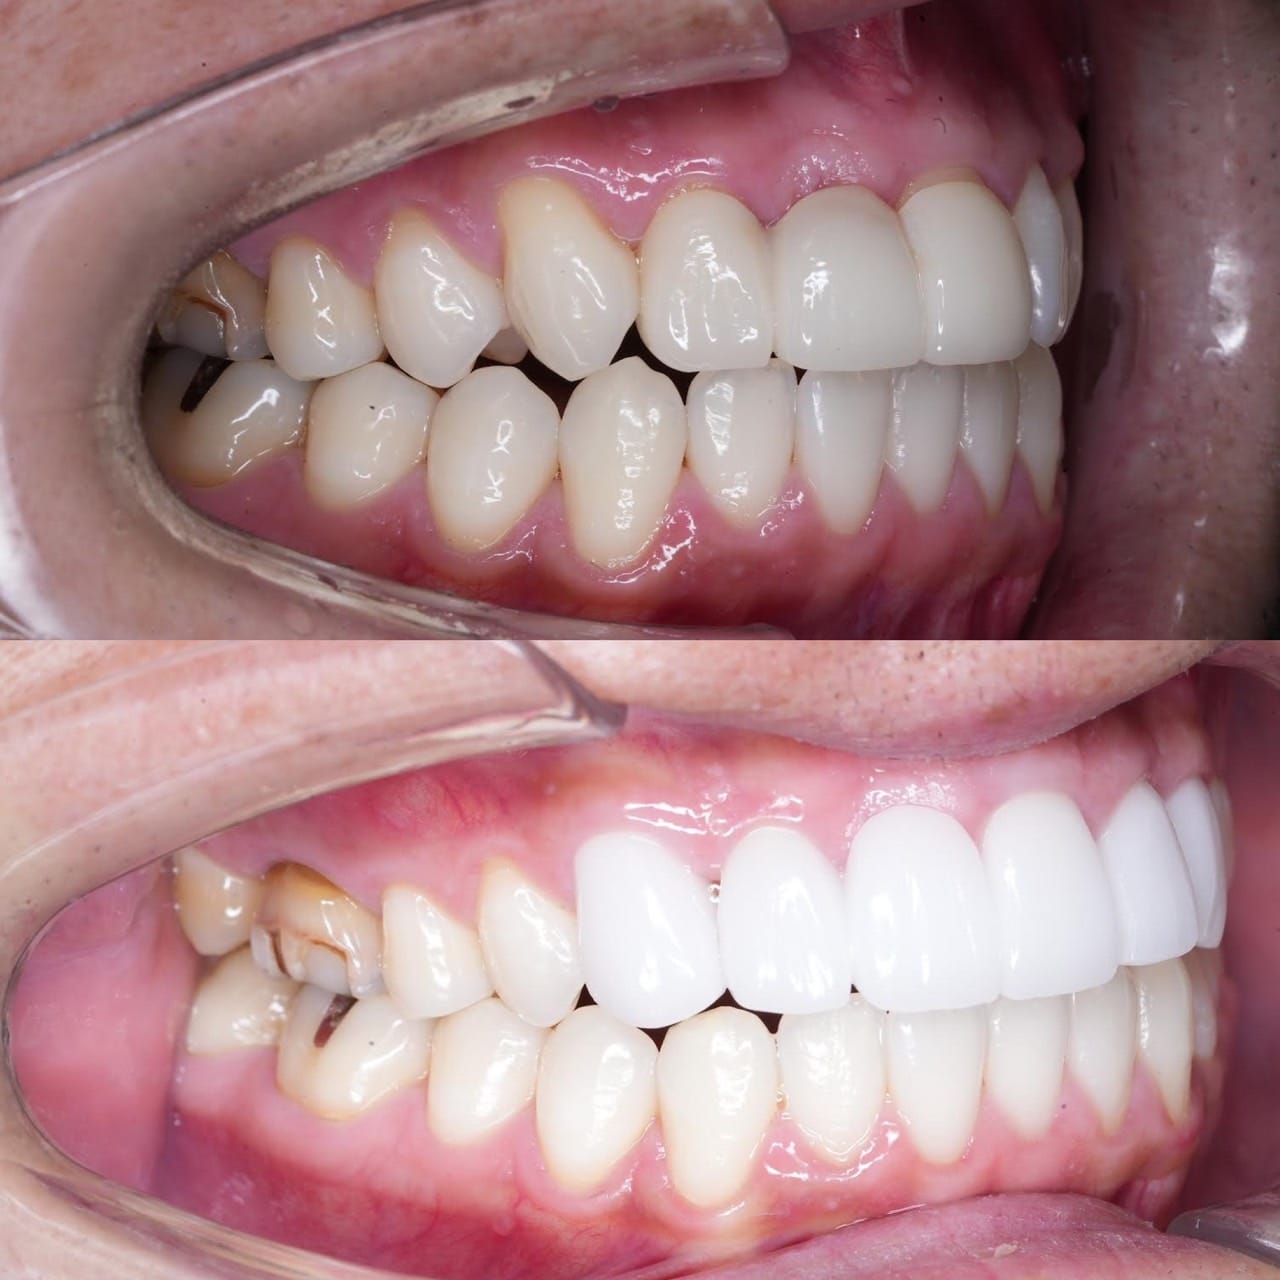

噛み合わせから審美的なところまで、トータルで治療させて頂いた患者様です。

ここまでやるとなると、できないクリニックもありますし、できるところでも年単位でかかってしまうクリニックが大半だと思いますが、今回は4月末にカウンセリングでご来院いただき、5月に治療をスタートして9月末には診療が終わっています。

治療回数や、治療期間がかかってしまうと、患者様も通院が辛くなったり疲れてしまったりしてしまうと思います。どんどん綺麗になっていく、食事がしやすくなっていくという実感がある方が患者様に楽しく治療に臨んでいただけると思うので、私は診療のスピード感を大切にしています。

トータルでやらせていただいたので、噛み合わせなどの機能面から外見などの審美性もかなり良くなり、患者様にも満足して頂けてよかったです。

治療期間 約4ヶ月